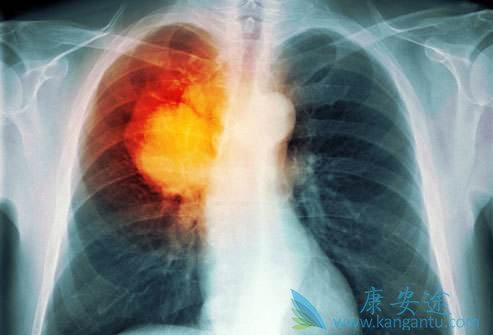

肺癌晚期治疗方案选择要参考患者情况

由于肺癌的生长部位、TNM分期、病理分型、基因分型、副癌综合征较为复杂,加之患者的年龄、体力状况评分(PS评分)、合并症等个体差异,其临床表现、治疗原则各不相同。特别是肺癌晚期患者的治疗就更要慎重。

目前第三代化疗药物联合铂类的双药化疗方案,提高了肺癌晚期治疗的效果,提高了晚期非小细胞肺癌患者的总生存期,但其疗效已达平台,很难有突破性的进展。随着分子生物学、药物基因学及高通量测序技术的发展和普及,个体化治疗是必然趋势。

多数肺癌晚期的患者丧失手术机会,且部分患者在传统放化疗的治疗中获益较少,尤其一部分患者存在大气道狭窄或梗阻、气管食管瘘等情况,药物治疗很难缓解症状。